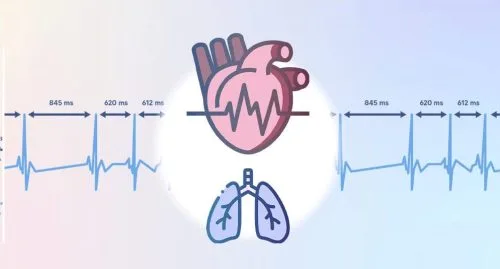

- تاکی آریتمی های قلبی

- برادی آریتمی های قلبی

- آریتمی قلب

- تپش قلب

- آریتمی های قلبی